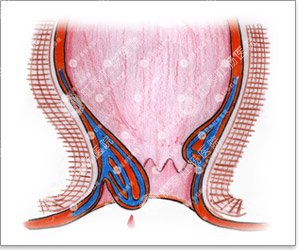

1、内痔:内痔容易与早期直肠癌混淆,因为二者都以无痛便血为主,但仔细观察,二者便血又有所不同。痔疮便血常见的是鲜红色的血,不与粪便相混而是附于粪块表面;也可表现为大便前后的滴血,严重的呈喷射状,多在大便秘结时发生。